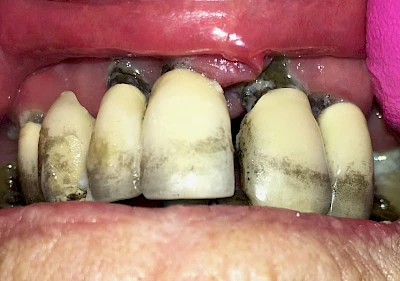

Bräunliche Verfärbung

Äußere Verfärbungen durch Genußmittel oder Medikamente (Eisen!) lassen sich meist nur durch den Zahnarzt z. B. mit einer professionellen Zahnreinigung entfernen.